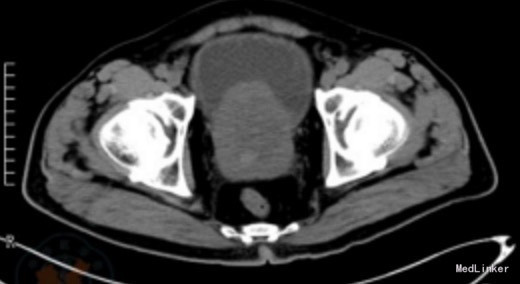

直肠指诊:前列腺Ⅳ度增大,质地韧,未触及结节。超声检查提示双肾轻度积水,膀胱小梁、小房形成,前列腺大小76 mm×72 mm×65mm。 盆腔CT平扫显示前列腺重度增生并突入膀胱内(图1)